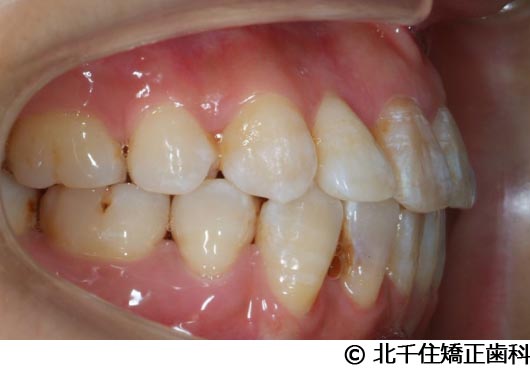

【症例5】上顎前突

- 治療前

- 治療後

- 治療名

- 上顎前突

- 費用

- 1,263,600円(税込)

- 期間

- 2年8ヵ月

- 治療回数

- 32回

- 通院頻度

- 1ヵ月ごと

- 年齢

- 13歳3ヵ月(初診時)

治療内容

-

患者様の症状

主訴:出っ歯

治療方法

骨格性の上顎前突、ヘッドギアを併用して上下顎第一小臼歯4本抜歯してワイヤー矯正。

治療結果

骨格性上顎前突に対し、ヘッドギアおよび抜歯を併用した矯正治療により歯列および咬合関係の調整を行った症例である。

治療後は保定装置を使用し、歯列および咬合の安定維持を目的として定期的な経過観察を行っている。

※治療結果は個人差があります。

治療を行う上での注意点(リスク・副作用)

歯磨き不良に伴うカリエスや歯周病、歯根吸収など。